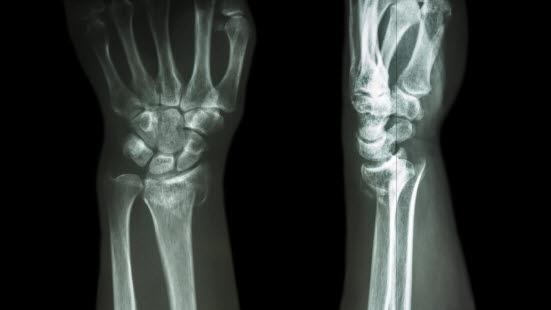

Røntgenbilder tatt forfra og fra siden bekrefter diagnosen (se over). Man ser etter feilstillinger, om det er brudd som innbefatter selve håndleddet, om det er ujevnheter i leddspalten, eller om det foreligger andre beinskader.